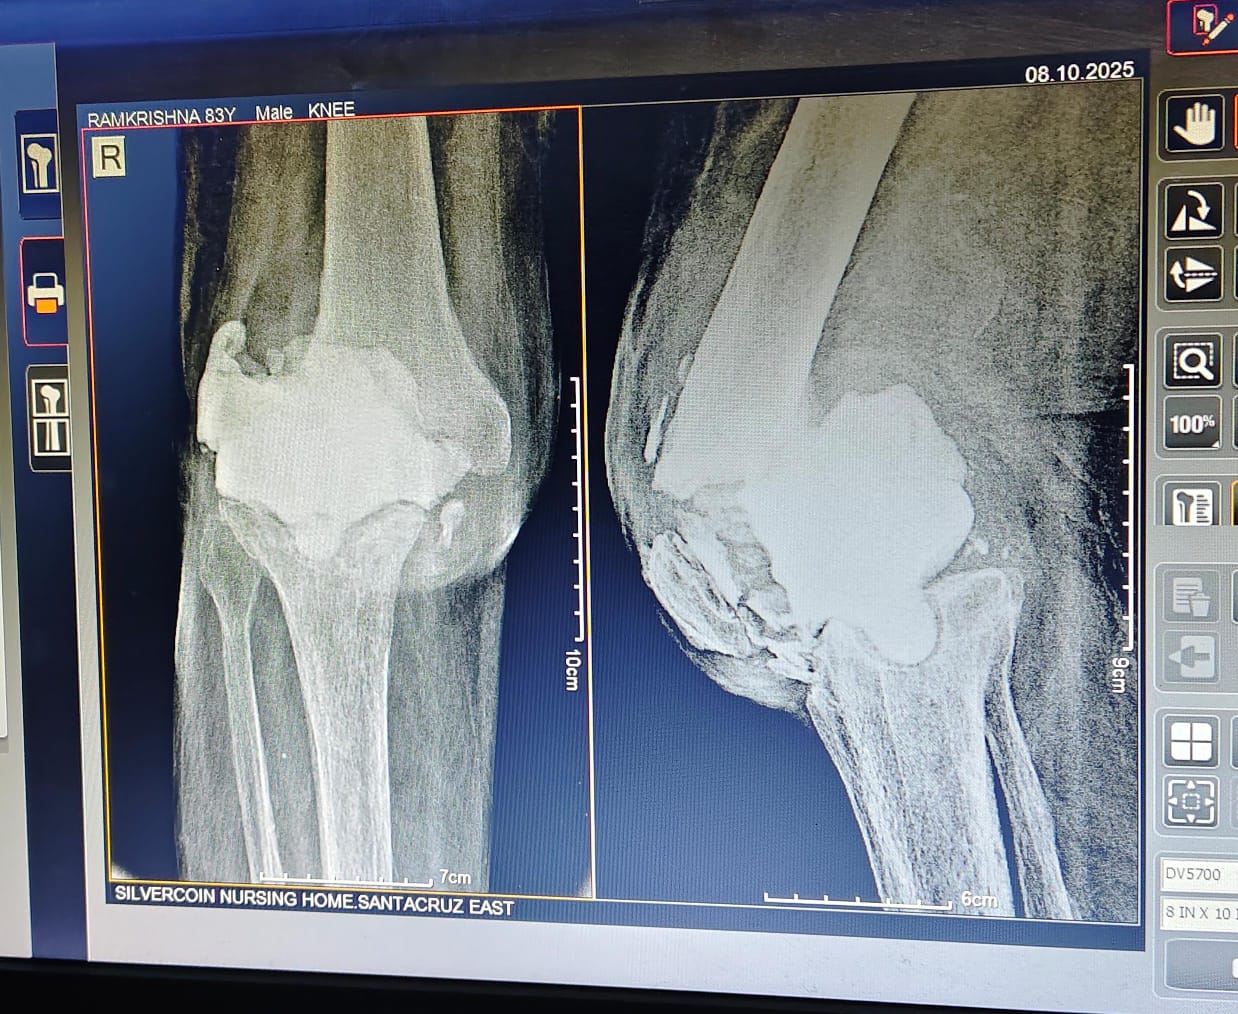

Dr Ajay Randive : IS MS Ortho (Mumbai) MRCSI ( UK) Consultant knee, Hip ,& Spine Surgeon, Dr Ajay Randhive is a eminent Knee, Hip , & Spine Surgeon practicing in to areas Andheri East,Santacruz East. Dr Ajay Randive did his MS Ortho residency from LTMMC, Sion Hospital Mumbai. He did overseas training in UK from 2003 till 2008. He is trained in total Knee Replacement, Hip Replacement, Revision Hip Replacement And Revision Knee Replacement Surgeries. He has worked at The Royal London Hospital. IN London where he worked a clinical fellow in joint Replacement unit. He has carried out more than 5000 Knee Replacement surgeries, 2500 Hip Replacement Surgeries, More Than 500 Revison Knee And Hip Replacement Surgeries 600 Spine surgeries & more than 1500 arthroscopic surgeries (Knee & Shoulder).